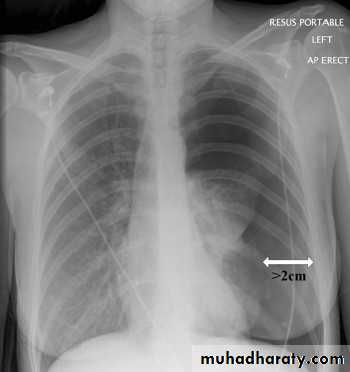

case 1

The chest X-ray shows thesharply defined edge

of the deflated lung with

complete translucency

(no lung markings)

between this and the

chest wall.

Size of PNX (small or large?)

The British Thoracic Society guidelines define a small pneumothorax as less than 2cm distance from the lung edge to the chest wall, and a large pneumothorax as equal to or more than 2cm.A two centimetre pneumothorax corresponds to a volume loss of 50%, and is regarded as an objective indication for treatment.